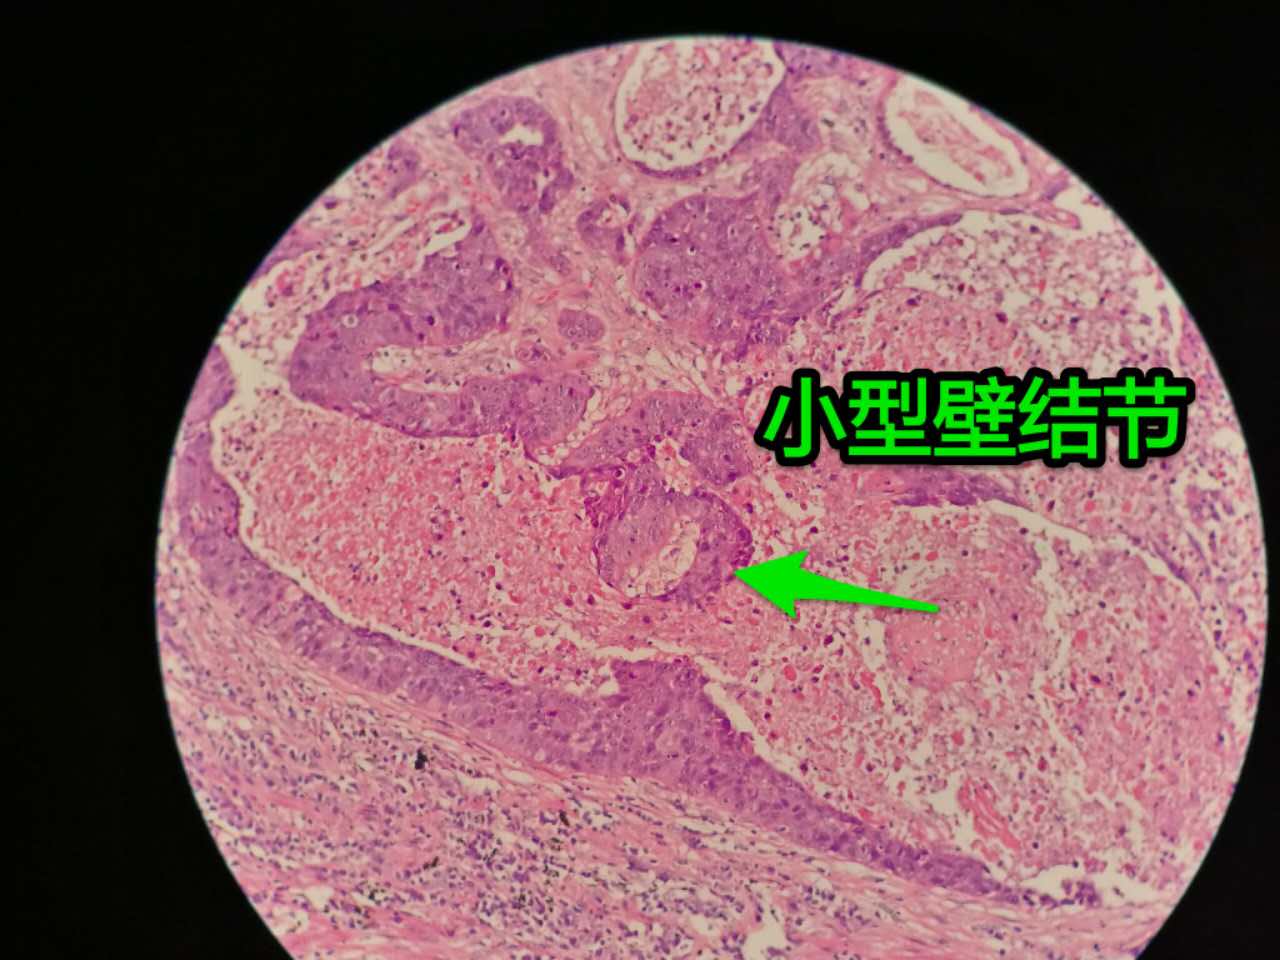

一侧常有突起,也就是壁结节。

壁结节不必等到空洞形成才判断,有坏死区就可以在增强片上判断有无壁结节

这个中央那块也算是小型的壁结节,肿瘤组织突入坏死区。或者说,这块肿瘤组织没坏死。